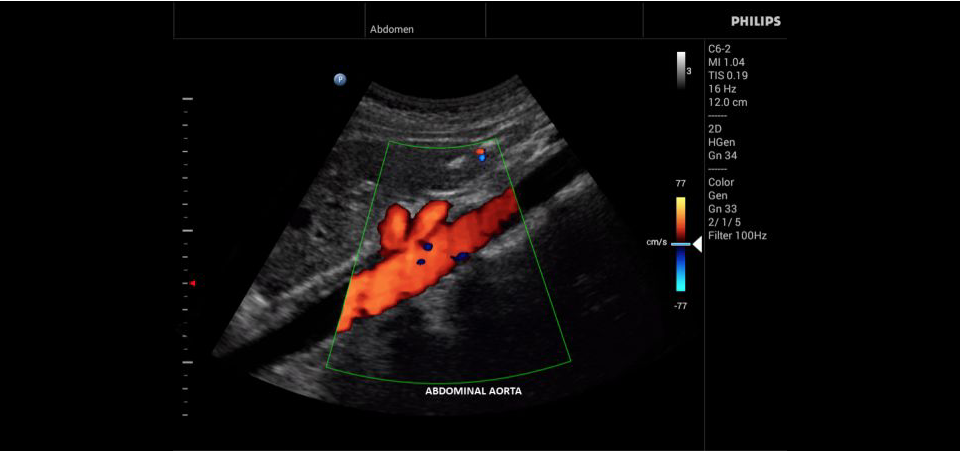

Philips InnoSight

Philips InnoSight увеличивает возможности сканирования во множестве мест оказания медицинских услуг. Благодаря данному УЗИ аппарату врачи могут не сомневаться в быстром выполнении обычных ультразвуковых сканирований во врачебном кабинете, клинике или больнице.

• Исследования сосудов;

• Цветное допплеровское картирование

• Конвексный УЗИ датчик Philips С6-2